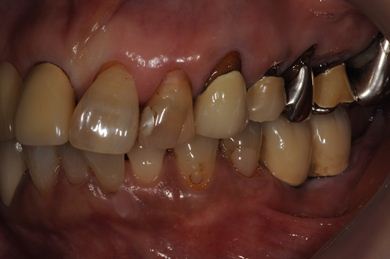

治療前

• 治療前